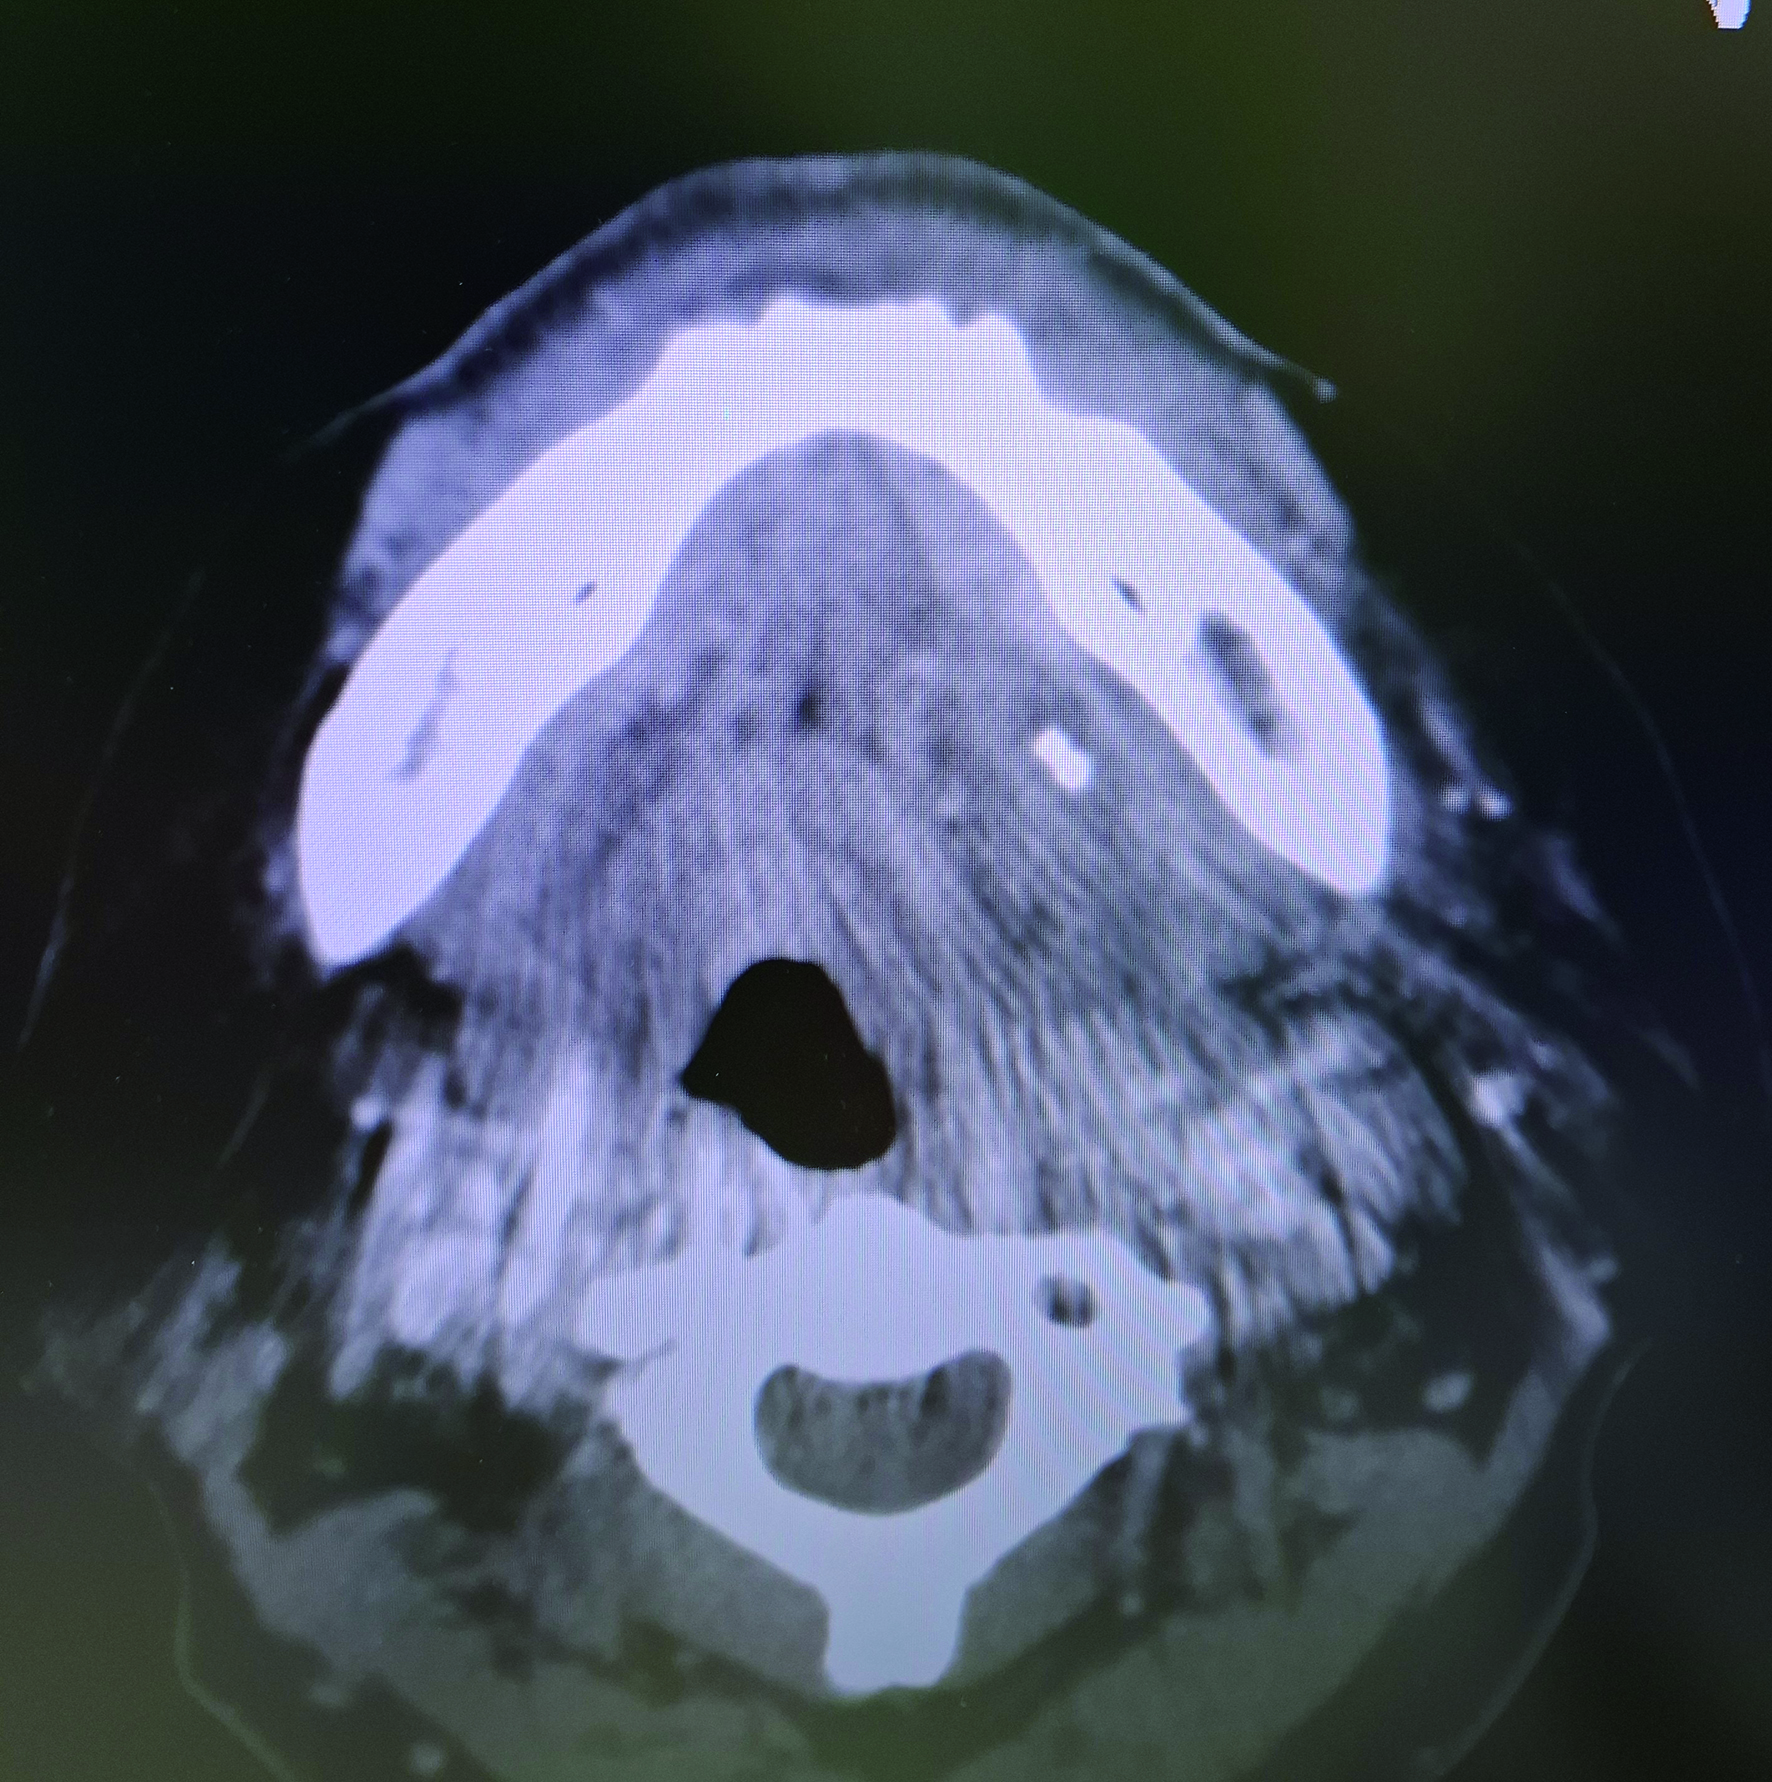

● 唾液腺結石(特別是下頷下腺、腮腺)

● 內視鏡檢查:將唾液腺專用內視鏡伸入導管